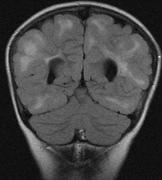

Neurologic Findings INTRACRANIAL LESIONS. Mental retardation and seizures in TSC are often associated with benign CNS astrocytic hamartomas.131 On imaging, the cerebral lesions show three patterns:132

SEIZURES. Typically observed first in infancy, seizures are a common presenting sign of TSC and a frequent source of morbidity. The seizures often begin as “salaam spasms”—repetitive myoclonic spasms that produce head nodding with associated extension/flexion of the trunk and limbs. They often progress to grand mal seizures25,116 and may be difficult to control. Vigabatrin has been advocated for control of infantile spasms but it carries a risk for irreversible visual field loss. Other treatments include corticosteroids, adrenocorticotrophic hormone, and a ketogenic diet.25,137–139 Selective surgical excision of an “epileptogenic tuber” may be an option for intractable epilepsy.140 MENTAL RETARDATION. Mental deficiency, part of Vogt's diagnostic triad (adenoma sebaceum, epilepsy, mental deficiency),3 affects about 50% of patients overall.25,141 TSC2 mutations may carry a higher risk than TSC1.142 AUTISM. This may affect 50% to 60% of TSC patients, possibly correlating with numbers of cerebellar and temporal tubers.25,143,144 Visceral Findings Patients with TSC may have renal, cardiac, pulmonary and other visceral involvement. RENAL. The TSC2 gene was localized by linkage with the polycystic kidney disease gene in patients with TSC and polycystic kidneys. This represents a contiguous gene syndrome in which adjacent genes (PKD1 and TSC2) are deleted together.145–147 Multiple angiomyolipomas of the kidney are benign hamartomas of blood vessels, smooth muscle, and fat. By 10 years of age, the frequency of angiolmyolipomas is 75%, similar to adults.148 The fat signal of angiomyolipomas helps to distinguish them from renal cell carcinoma.25 Renal insufficiency/failure may be the complication of both cystic disease and angiomyolipomas and is one of the leading causes of morbidity and mortality in TSC.138,149 CARDIAC. Rhabdomyoma are usually multiple, typically asymptomatic, and often regress with age.150,151 PULMONARY. Lymphangioleiomyomatosis is a progressive lung disease characterized by bronchiolar smooth muscle infiltration and cystic changes of the lung parenchyma. About 1% of adult females with TSC are affected.116,152,153 OPHTHALMIC FEATURES The principal ophthalmic manifestations of TSC are in the posterior segment. Astrocytic Retinal Hamartomas Although in Van der Hoeve's original description the term phakoma or phakomata was a generic term for the tumors occurring in various organ systems,1 it has become associated with the retinal astrocytic tumors of TSC,3 which occur in about 50% of affected patients and are bilateral in 25% to 30% (Table 3, Fig. 16).154,156

Two genes have been identified, TSC1 (9q34, OMIM #605284) and TSC2 (16p13.3, OMIM #191092), which appear to be tumor-suppressor genes. The gene product of TSC1 is hamartin and the gene product of TSC2 is tuberin. Of sporadic cases of TSC, 70% have been linked to TSC2 mutations. Among the familial cases, half are linked to the 9q34 locus and half to the 16p13.3 locus. Hamartin and tuberin appear to interact together in vivo, which may be why mutations of two different genes produce a similar phenotype. Together they form a cytoplasmic protein complex that has an inhibitory effect on cell growth and division. The tuberin-hamartin complex inhibits the activity of TOR (target of rapamycin). This has raised the possibility of reestablishing the regulatory effect of the tuberin-hamartin complex on TOR with drugs such as rapamycin.115,164 |